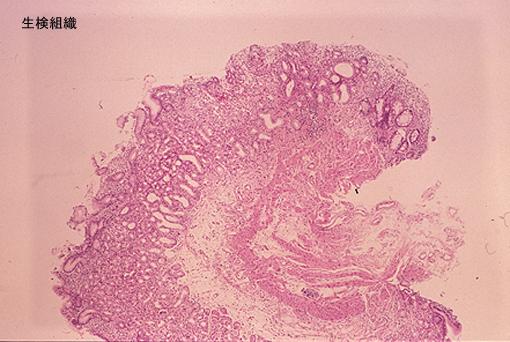

Mucosa Gástrica que se evidenció en Recto.

[Image-ID:7693]

Lesión que asemeja tumoración/Mucosa aberrante

colon/recto

Micro

10 - 14